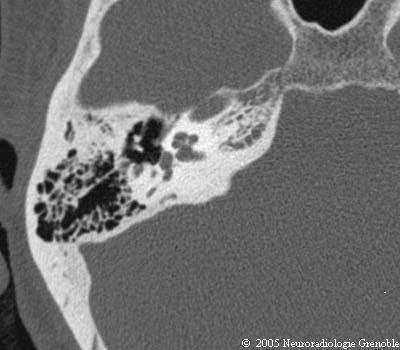

Radioanatomie TDM du rocher normal

Méat acoustique interne

Cochlée

Vestibule

Canal semi-circulaire postérieur

Ampoule du canal semi-circulaire post.

Fenêtre vestibulaire (ovale) et platine

Canal de Morgagni

Aqueduc du vestibule

Marteau (col)

Enclume (longue apophyse)

Etrier (branches)

Canal du facial et muscle de l'étrier

Canal du muscle du marteau

Ligament antérieur du marteau

Mésotympan

Sinus tympani (volume partiel)

Antre